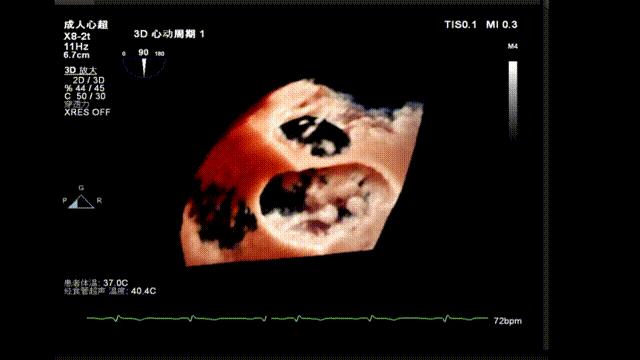

术后TEE显示二尖瓣双孔化形成,瓣膜夹稳定